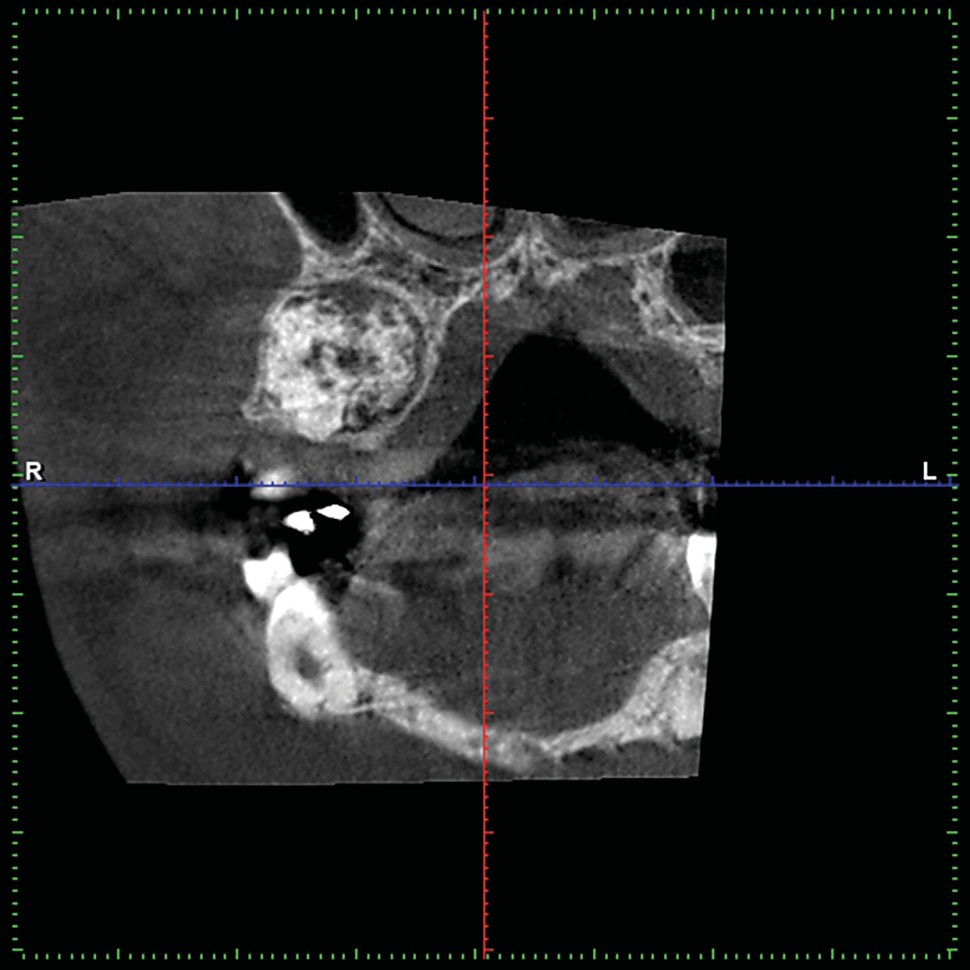

Un CBCT est pratiqué : la périphérie de la lésion ne présente pas de réaction ostéoclérotique (fig. 2) et on retrouve un liseré radioclair « ceinturant » la lésion (fig. 3).